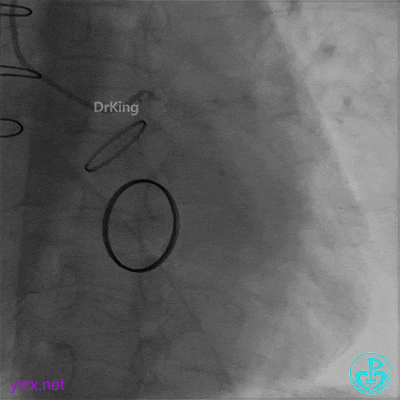

05 急诊冠脉造影

前降支血流3级,前降支近段、对角支开口大量血栓,回旋支开口闭塞。